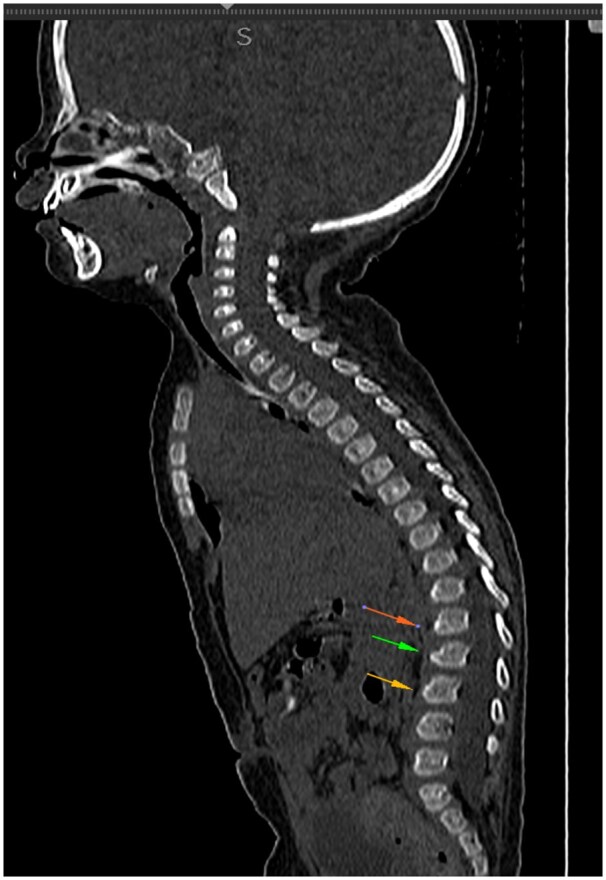

单唾液-四己糖神经节苷脂,也被称为婴儿GM1神经节苷脂病,是一种常染色体隐性溶酶体储存疾病,由GLB1基因突变引起,该突变阻止了β-半乳糖苷酶的工作。我们讨论了一例婴儿GM1神经节脂质沉积症,其表现为异常的身体运动,背部和臀区广泛的皮肤黑色素细胞增多,面部特征粗糙,以及大头畸形。影像学表现为第二、第三、第四腰椎前下喙状突起,非对比CT显示双侧丘脑高密度。在T2加权图像上,白质和皮质下U纤维持续高信号强度,表明双侧丘脑体积大,T2低,髓鞘形成明显受损。β-半乳糖苷酶活性降低证实了诊断。

Mono-sialo-tetra-hexosylganglioside, also known as infantile GM1 gangliosidosis, is an autosomal recessive lysosomal storage disorder caused by a mutation in the GLB1 gene that stops the β-galactosidase enzyme from working. We have discussed a case of infantile GM1 gangliosidosis which presented with abnormal body movements, extensive dermal melanocytosis over back and gluteal region, coarse facial features, and macrocephaly. Radiological features included antero-inferior beaking of second, third, and fourth lumbar vertebrae, bilateral hyperdense thalami on non-contrast CT. On T2-weighted images, there is a persistently high signal intensity of the white matter and subcortical U fibres, which indicates bilateral bulky thalami with T2 hypointense and significantly impaired myelination. Reduced β-galactosidase activity verified the diagnosis.